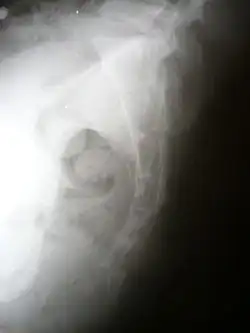

Lateral radiograph showing a fracture of the coccyx, as well as a lower lumbar fracture